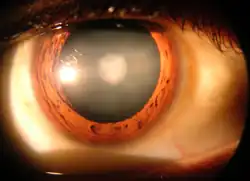

Die Katarakt (IPA: [][1], ), auch grauer Star, Linsenstar und Linsentrübung genannt, bezeichnet eine meist erworbene, selten angeborene Trübung der Augenlinse. Bei manchen Menschen mit fortgeschrittener Katarakt kann man den Grauschleier hinter der Pupille erkennen; daher kommt die Bezeichnung „grauer Star“, nicht zu verwechseln mit dem grünen Star, dem Glaukom. In der Regel werden die befallenen Strukturen mittels einer sogenannten Spaltlampe untersucht und beurteilt, was letztlich zur Diagnose führt. Subjektives Hauptsymptom ist der fortschreitende Verlust an Sehschärfe. Ist eine medizinische Indikation gegeben, besteht die Therapie der Wahl meist im operativen Ersatz der trüben Linse durch ein künstliches Linsenimplantat.

Das subjektive Leitsymptom ist ein langsamer, schmerzloser Verlust der Sehschärfe (Visus), insbesondere wenn sich die beginnende Trübung in zentralen Bereichen der Linse befindet. Es kommt zu Verschwommensehen und zunehmender Blendungsempfindlichkeit, da die diffuse Streuung den Bildkontrast reduziert und die Patienten ihre Umwelt „wie durch einen Nebel“ wahrnehmen. Zudem kann es zu einer reduzierten Farbsättigung kommen.

Gelegentlich treten auf einem Auge (monokular) Doppelbilder auf, die beim Schließen des anderen Auges weiterhin vorhanden sind. Um Lichtquellen werden Halos oder Lichthöfe beobachtet. Die Hell-Dunkel-Anpassung des Auges ist verlangsamt, und das räumliche Sehen kann beeinträchtigt sein.